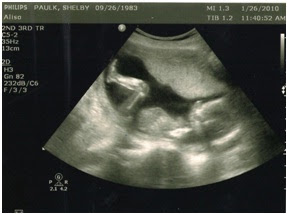

Meet our newest addition:

First and most important, the ultrasound showed a healthy baby!! God is so good and our prayers have been answered. We aren’t concerned on what the sex of the baby is, but more that we have a healthy baby! He/she had a strong heartbeat of 152 bmp and today was the first day we got to hear it. It makes the pregnancy seem so much more real and I also think I’ve been feeling the baby move for almost a week now (starting at about 15 weeks) which is the greatest thing ever.

We did go into the ultrasound asking wheather we were having another boy or another girl and that’s also the question we walked out of the room with. Even though it’s a little early to have an ultrasound, it wouldn’t have been too early to see the baby’s gender…if he/she would have cooperated. This little one had his/her legs crossed and covering its’ parts the entire time.

Once the technician checked everything out she went on to check the baby’s gender. Once she looked she said “Oh, I think it’s a boy” then she kept scanning and looking and about 2 minutes later she said “Uh oh…I actually think it’s a girl”… She thinks that the baby’s toes, that were in front of the private parts, were making the baby look like a boy, but she wasn’t sure. So after trying to get the baby to move for about 40 minutes we gave up…however, she did say she was leaning towards the baby actually being a GIRL because she thinks she saw “the three lines”, but she wasn’t going to say one way or the other just in case.